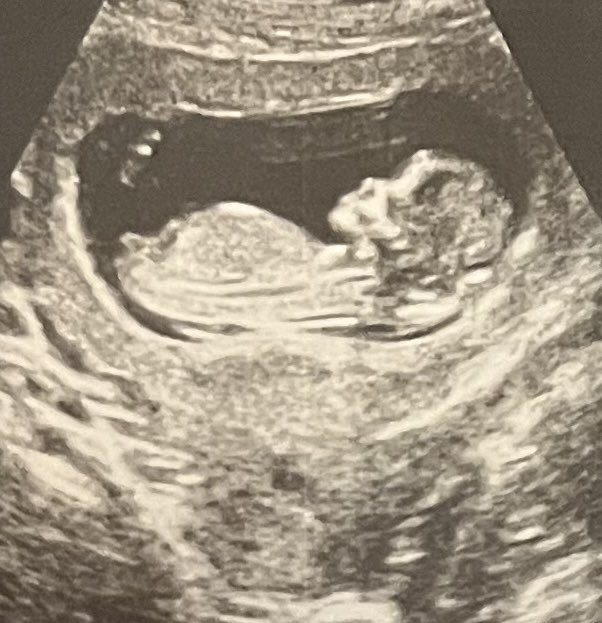

In the spirit of #blocktober, I wanted to show you what perfect spread around a popliteal sciatic should look like. @jeffgadsden 😂

Baby Kim #3: April 2024!

Possible names: Perry (short for peroneal), Psy (sciatic), Poppy (popliteal). @ASRA_Society #blocktober23